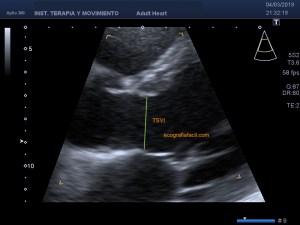

139. Ecocardiografía. Estudio Paraesternal Eje Largo.

141. Mediciones de los planos paraesternales.